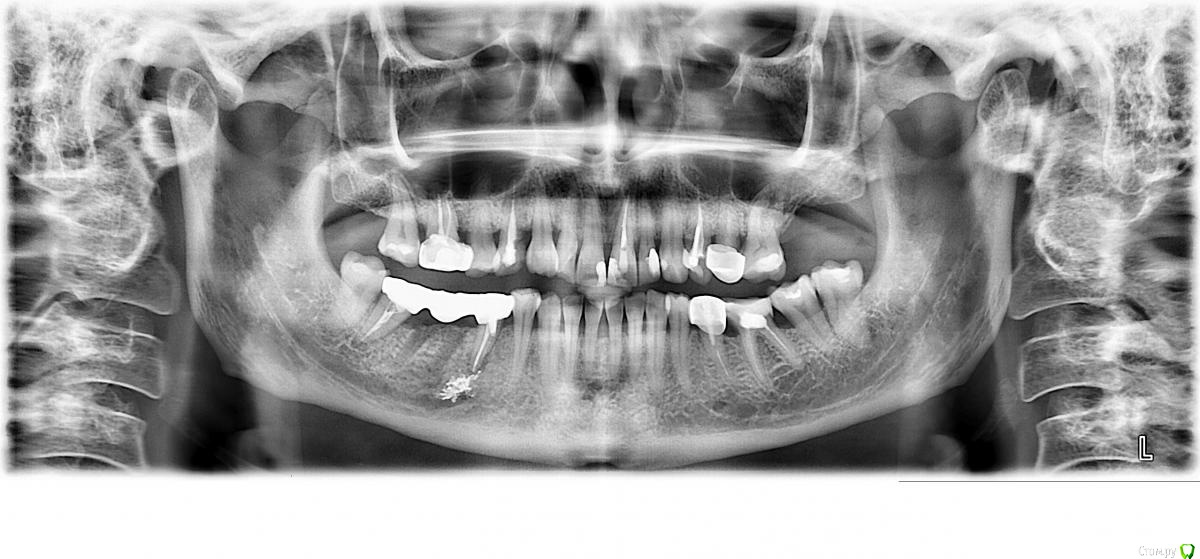

ян""ка Опубликовано 7 ноября, 2019 Поделиться Опубликовано 7 ноября, 2019 Здравствуйте, предлагают мост на четыре зуба с удалением 45го, но я знаю что такой мост уже менее прочен даже цельнолитой. Это так? Разболелась эта 5ка, болит при накусывании, прошло 4мес после постановки моста. А вообще, соседнюю 4ку уже видновато во рту, хотелось бы керамику. Что попрочнее, может посоветуете? Спасибо https://d.radikal.ru/d20/1911/dd/443834cb5940.jpg Ссылка на комментарий

ян""ка Опубликовано 25 ноября, 2019 Автор Поделиться Опубликовано 25 ноября, 2019 а можете, пжл, посмотреть еще - достаточно ли костной ткани на Ваш взгляд чтобы поставить имплант на 46м? Не страшно ли еще рядом с такими "залежами" под 45м что-то имплантировать? Ссылка на комментарий

red_butler Опубликовано 26 ноября, 2019 Поделиться Опубликовано 26 ноября, 2019 КЛКТ, правильно? да а тут что, совершенно ничего нельзя сказать? умеренный дефицит костной ткани по высоте, возможно потребуется закрытый синуслифтинг 1 Ссылка на комментарий